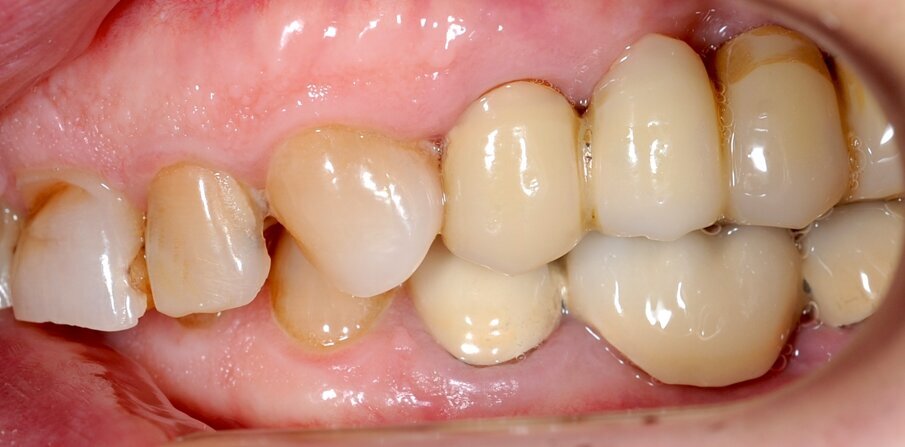

Il fresato ottenuto è poi riportato su articolatore Reference SL – già opportunamente programmato – e viene dall’Odontotecnico competente più precisamente funzionalizzato secondo i criteri della programmazione funzionale sequenziale, evidenziando con cere colorate i rapporti di centrica, le funzioni di mediotrusiva e protrusiva e le protezioni retrusive. I monconi sfilabili consentono la modellazione della sequenzialità mediotrusiva con la guida incisale indicata dalla registrazione axiografica (blu) (Figg. 34-37). La ceratura sequenziale è ora scansita con Sirona InEos X5 su Exocad, ed il modellato viene ricontrollato al CAD per spessori, connessioni e morfologia, e nella regolazione degli offsets per la ripreparazione dei monconi, ed è inviato al CAM per la fresatura dei II provvisori in Bredent breCAM.multicom, un PMMA con microriempitivo ceramico ad alta stabilità, su Dental Plus 5 Axis Milling Machine. La rifinitura dei monconi è seguita da ribasatura dei II provvisori in TRP - previo isolamento di tutte le superfici funzionali - e gli stessi sono poi rifiniti e lucidati. I soli elementi 3.3, 4.2 e 4.3 sono rimodellati in regione incisale con addictions in composito, secondo la morfologia studiata in ceratura. La consegna conferma la buona integrazione dei manufatti dal punto di vista estetico, occlusale, articolare e neuromuscolare, con controllo occlusale conforme al progetto (Figg. 38-42).

Il paziente utilizza questi secondi provvisori per otto settimane, durante le quali conferma la buona integrazione dei restauri e la soddisfacente funzione occlusale. Ciò è verificato con l’esecuzione di una nuova axiografia elettronica che già a due settimane dalla consegna evidenzia una buona risposta muscolare al nuovo design occlusale ed alla nuova postura mandibolare in TRP (Figg. 43-46). Provvediamo infine alle impronte per la costruzione dei manufatti definitivi in Zirconia-ceramica. I modelli sono scansiti in laboratorio con inEos X5 (Dentsply Sirona) su exocad (Figg. 47-49), ed una seconda scansione viene eseguita con i provvisori del Paziente posizionati sui modelli (Figg. 50-52). Il CAD consente di eseguire un matching fra le due scansioni, per cui i secondi provvisori utilizzati in TRP, con funzione occlusale sequenziale già completamente programmata, sono utilizzati per definire le morfologie dentali definitive di tutti gli elementi da restaurare (Figg. 53, 54) secondo il rapporto intermascellare definito (Figg. 55-58). Si esegue quindi fresatura al CAM della protesi definitiva in zirconia (Figg. 59, 60), la stratificazione e finitura ed infine la consegna al Paziente con cementazione in Panavia V5 (Figg. 61-65).